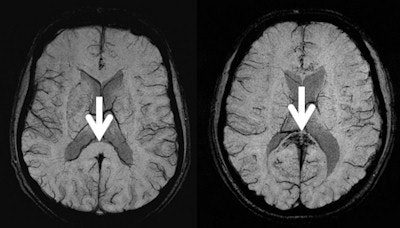

"In most cases, these microhemorrhages are so small that they are only visible with susceptibility-weighted imaging," Knauth said. "With this technique, the microhemorrhages are depicted as little black spots."

The MRI results showed brain microhemorrhages almost exclusively in HACE survivors. Of the 10 climbers with a history of HACE, eight had evidence of microhemorrhages on MRI. The other two had uncertain results. Only two of the remaining 26 climbers were positive for microhemorrhages.

Survivors of the most clinically severe cases of HACE had the most prominent evidence of microhemorrhages on MRI, according to the research group. The bleeds were found predominantly in the corpus callosum, which consists of densely packed nerve fibers connecting the two brain hemispheres, and they showed a characteristic distribution different from other vascular diseases such as vasculitis.